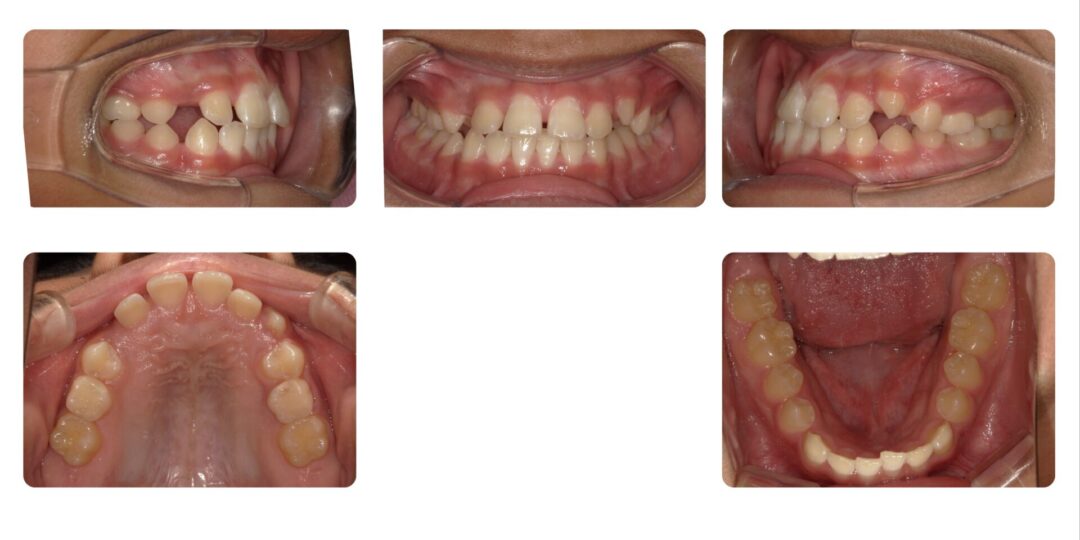

矯正治療後

反対咬合、正中離開が気になる

第一期治療 上顎拡大床

1年7か月